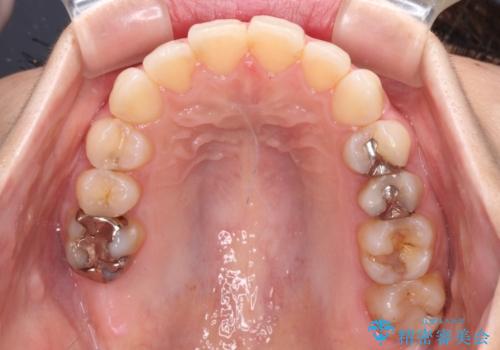

- 前歯のデコボコを気にして来院された患者様です。

主に下顎歯列全体の後方移動とIPR(歯と歯の間を削る)によってデコボコが解消するように設計し、インビザラインにより治療を行うこととしました。

舌突出癖がある方ですと、叢生が解消すると同時に前方に拡大されてしまいますが、ゴムかけをしっかりと行ってくださったこともあり、スッキリとした仕上がりとなりました。